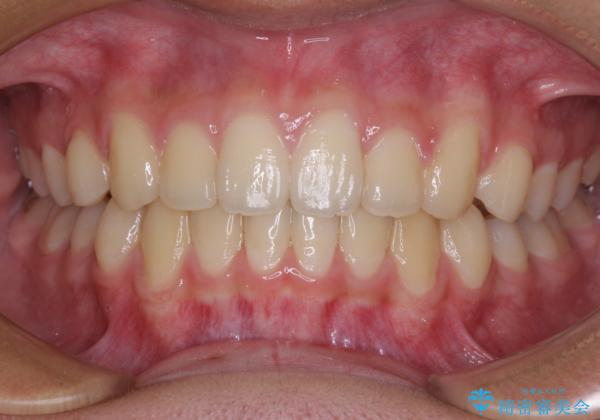

前歯の隙間とデコボコを改善 高校生のインビザライン治療

- 前歯のデコボコと隙間を気にして来院された高校生の患者様です。

下顎前歯が上顎前歯を突き上げるような咬み合わせとなっており、その影響で上顎正中に隙間ができている状態でした。

叢生の程度は軽度であり、本人もしっかりと使用する自信があるとのことだったので、インビザラインによる矯正治療を行うこととしました。

突き上げによる隙間を予防する為に、深い咬み合わせを改善するような治療計画としました。咬み合わせを改善させることはできましたが、隙間は後戻りしやすいので、通常の下顎前歯のみではなく、上顎前歯2本もワイヤーで保定を行いました。